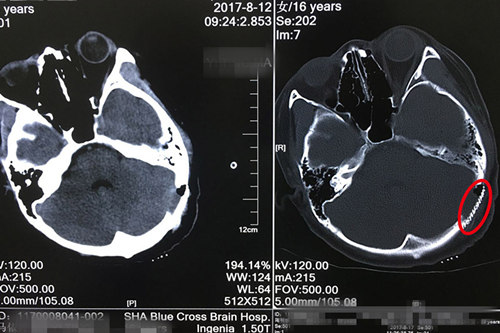

術后CT顯示:鈦網(wǎng)與顱骨結(jié)合緊密,未見明顯異常病灶。

取枕下中線并向左枕部反7字行切口,上端自枕外隆突上2公分,下端達發(fā)跡內(nèi),長約15cm,逐層切開,翻轉(zhuǎn)皮瓣,見左枕骨有1.5*1.0cm顱骨缺損,囊腫經(jīng)缺損處突入腦內(nèi),擴大骨窗大小約3.0*3.0cm。剪開硬腦膜放出部分腦脊液,腦壓下降。腫物包膜完整,切開囊壁,見囊內(nèi)容物為豆腐渣樣及毛發(fā),取出內(nèi)容物,囊壁與腦組織有粘連,與硬腦膜粘連明顯,分離并完整切除囊壁,探查瘤腔無殘留腫瘤及出血,生理鹽水沖洗術野,殘腔壁止血紗布貼敷,人工硬腦膜一片覆蓋,取大小約3.0*3.0cm鈦網(wǎng)及4枚鈦釘行顱骨修補,硬膜下置硅膠引流管一枚。清點腦棉及器械如數(shù),腦壓不高,緊密逐層縫合頭皮各層,術畢。